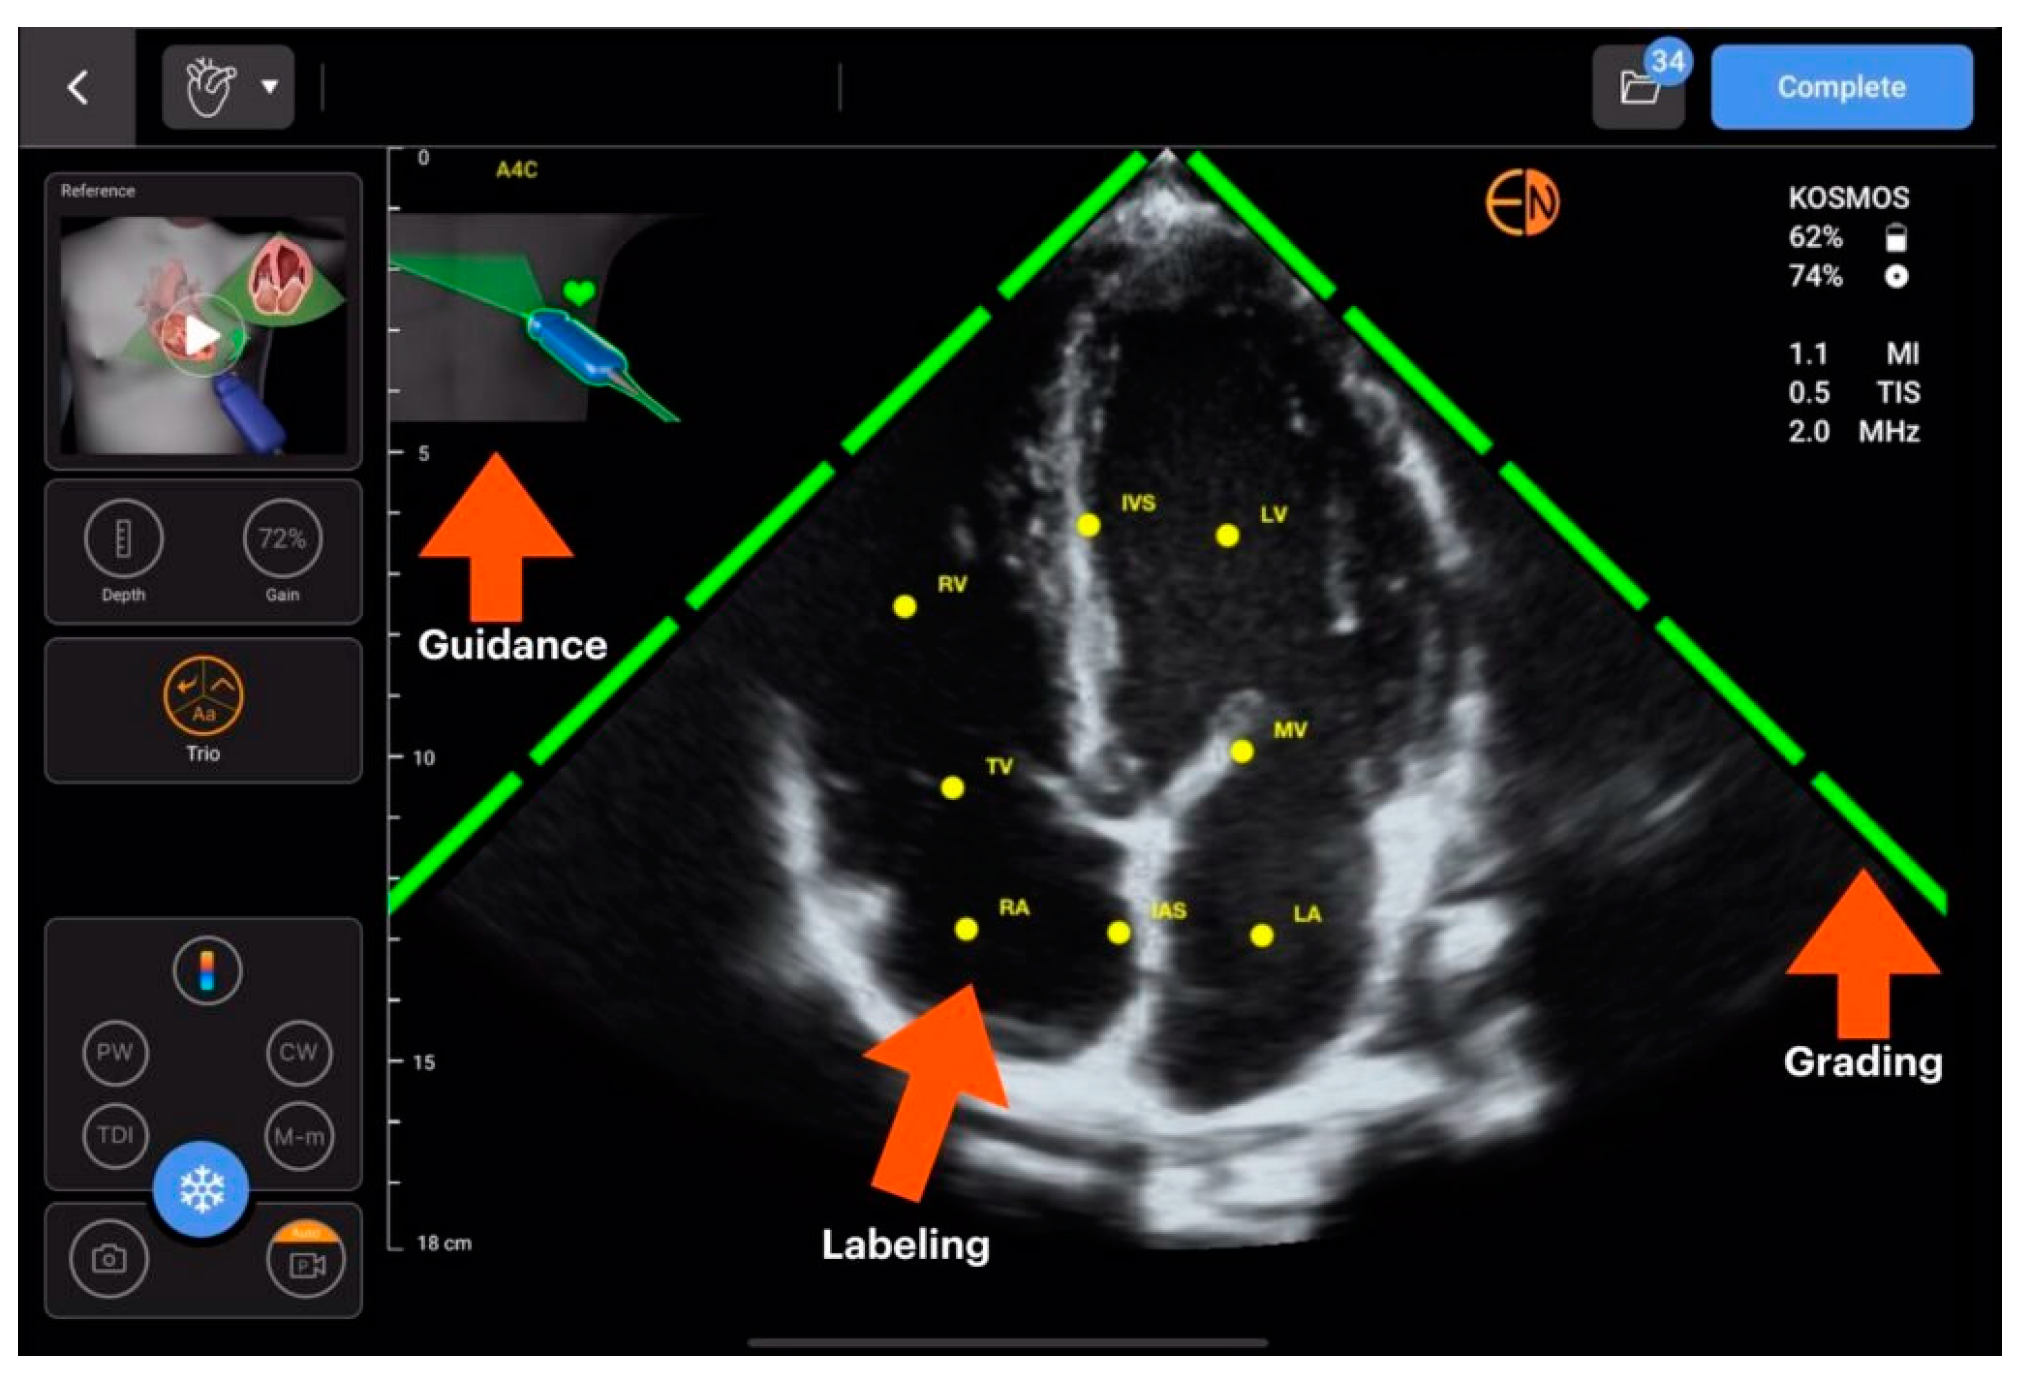

| SmartEchoVue | Mindray | assessment of views | Whole body |

| Us2.ai and AI TRO | EchoNous | ||

| Butterfly ScanLab | Butterfly Network | ||